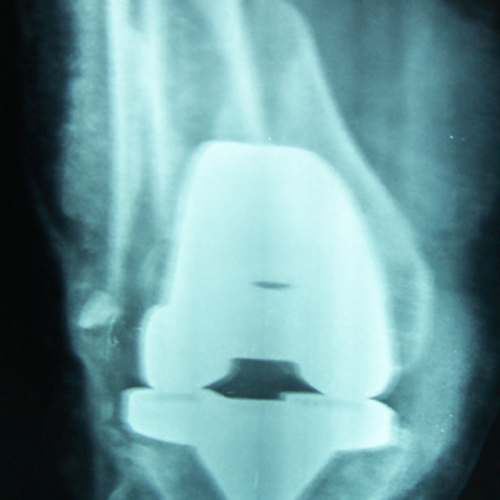

Case:14 Periprosthetic Fracture

60 years old patient with total knee replacement on left knee presented with open grade 1 injury. Debridement & slab given on emergency bases. Fixation with plate & screws done. Union was seen after 6 months.

Pre-Op AP

Pre-Op Lat.

Immdiate Post-op

1 and half months Post-op

2 and half months Post-op

3 and half months Post-op

4 and half months Lateral

6 Years Follow-Up